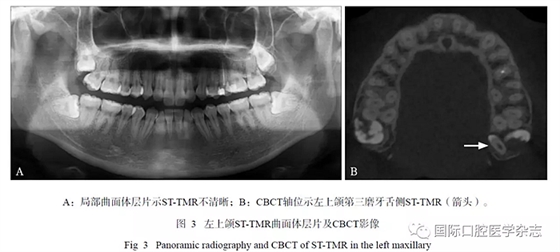

16例ST-TMR患者的CBCT顯示:21顆STTMR中埋伏阻生者占多數(shù)(18/21),3顆萌出(3/21);18顆埋伏阻生ST-TMR多數(shù)與第三磨牙同時(shí)阻生(10/18);萌出者2顆位于第三磨牙頰側(cè),1顆位于其方。ST-TMR位于第三磨牙遠(yuǎn)中較多(9/21),其余分布在第三磨牙的周圍且變化較大,如第三磨牙近中、頰(舌)側(cè)、根(冠)方;5顆ST-TMR緊鄰上頜竇底壁,1顆進(jìn)入翼上頜裂。位于腭側(cè)ST-TMR的CBCT較曲面體層片顯示更清晰(圖3)。